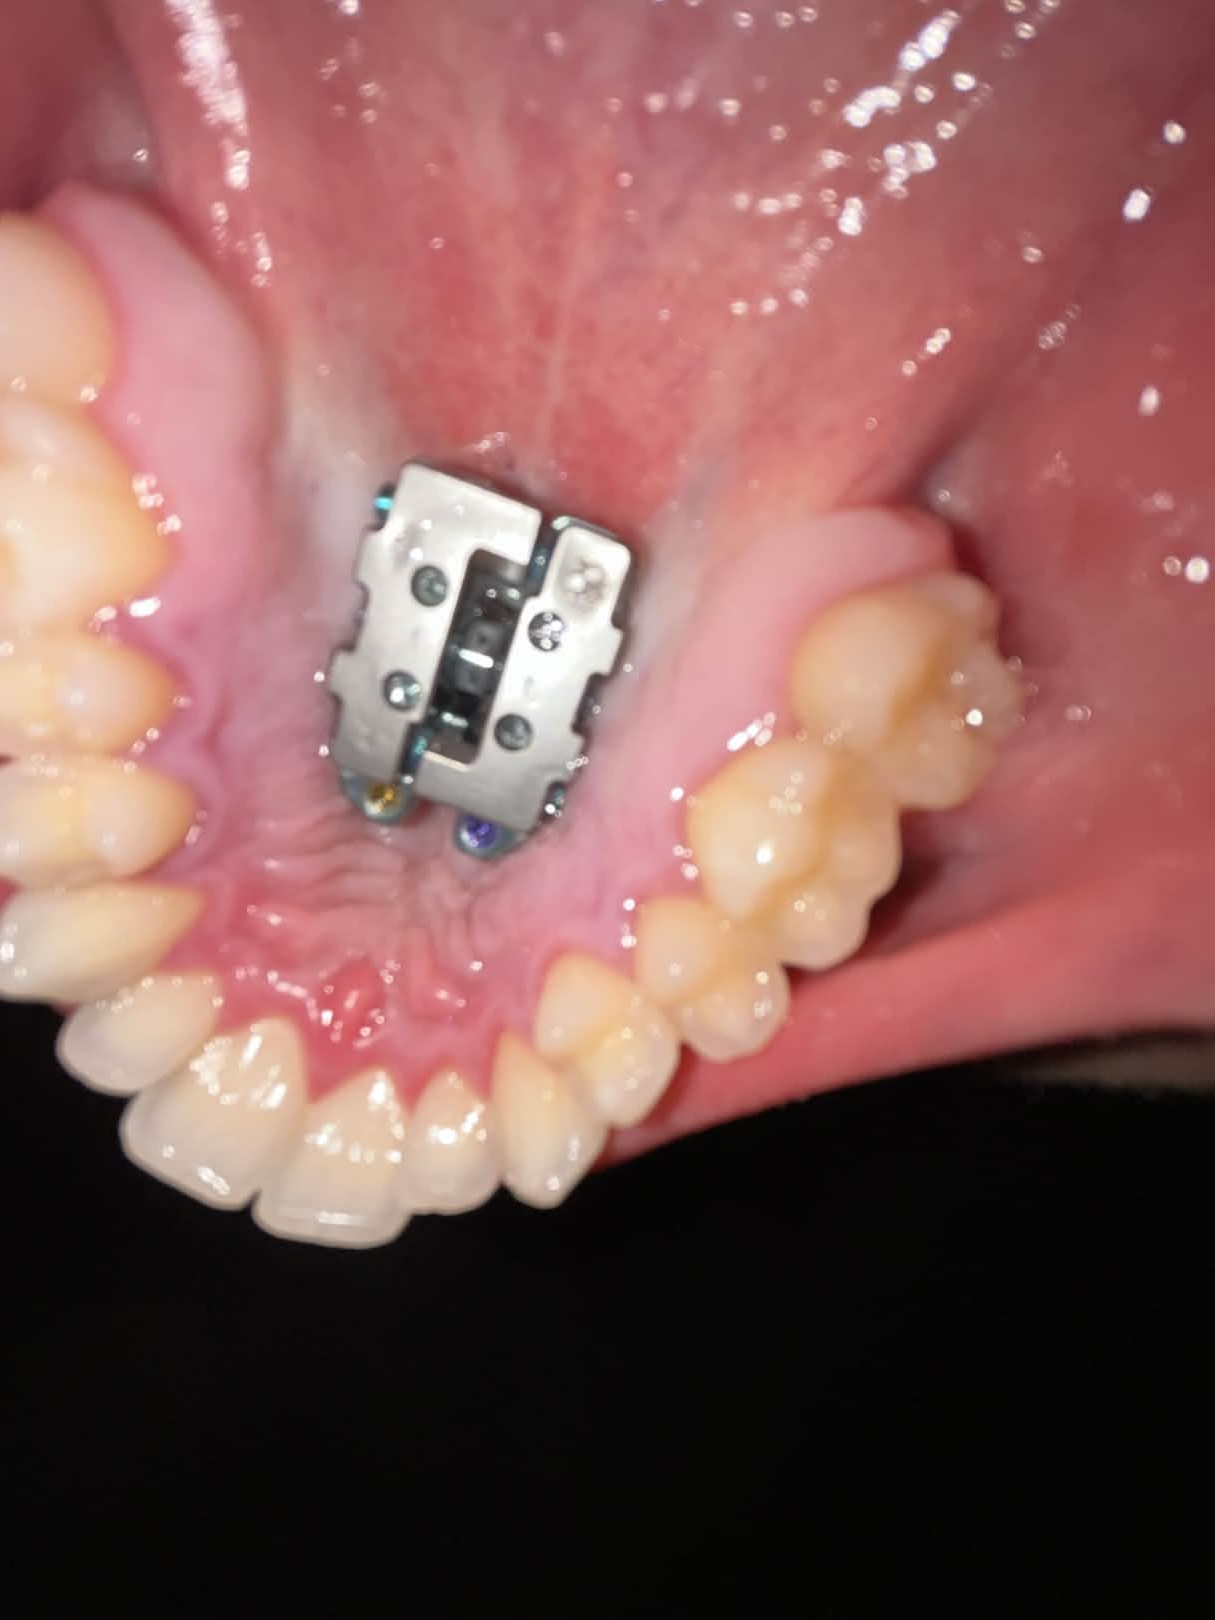

$27K Custom 8 TAD FME Pro finally installed on my guy Brandon

from Dr. Jaffari ofc

Best expander on the market currently.

For those who aren't familiar with the custom FME devices, I suggest watching the video below to truly understand its power.

"Waiting for the professional pics + CBCTs from Dr Jaffari, but just had the 8 TAD FME Pro finally installed. Wasn’t too painful, feeling a lot of pressure on my maxilla rn tho. 1 turn a day for now until I split, aiming for ~8mm expansion. Expecting trimax in about 11 months as long as I split quickly"

Pure controlled palatal expansion with significant midface expansion.